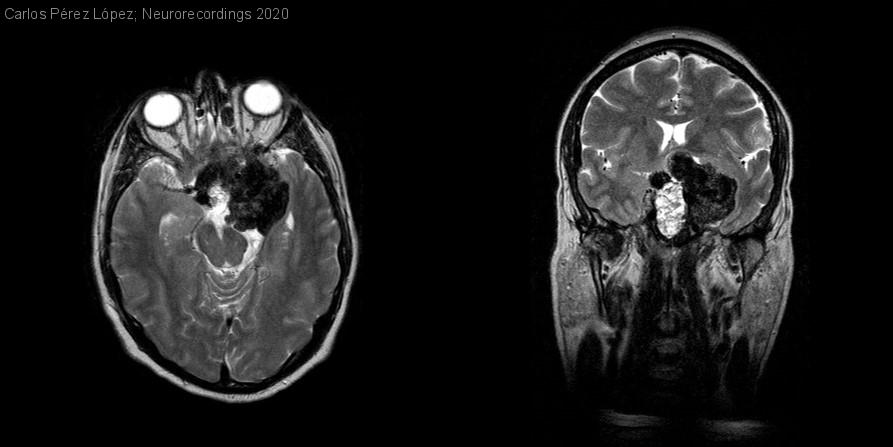

Prolactinoma gigante calcificado

Hombre | 63 años

Diagnóstico final: Prolactinoma

Varón de 63 años, con antecedentes de hipercolesterolemia, hipertensión arterial e hipotiroidismo primario autoinmune, refiere pérdida visual progresiva de dos años de evolución. La campimetría muestra déficit temporal en el ojo derecho y amaurosis del...